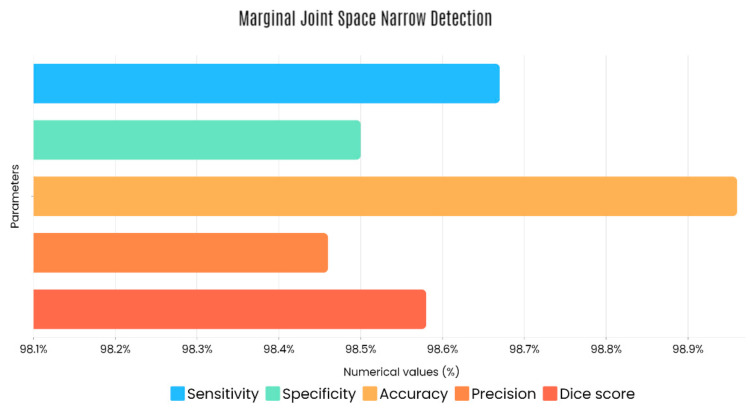

Sample images of the marginal joint space narrowing region of interest can be seen in Figure 5. The IoU (Intersection of Union) metrics were used to evaluate our region of interest detection system. This metric was the size of the intersection between the area of the actual bounding box and the area of the predicted bounding box divided by the size of the area of both boxes added together. When the IoU was 0.70, the narrow marginal joint space was found in 99.72% of the knee joints using our presented model. Additionally, Figure 6 depicts the ROC curve for marginal joint space narrow detection. The results of the presented marginal joint space narrow detection model obtained a sensitivity rate of 98.67%, a Dice score of 98.58%, a precision rate of 98.46%, a specificity rate of 98.50%, a false positive rate of 0.0100, a false negative rate of 0.0197, and an overall accuracy rate of 98.97%, as shown in Table 6, and the graphical illustration of Table 6 values is depicted in Figure 7. Table 7 demonstrates the metric performance outcomes of the proposed ResNet101 and VGG16 model to classify the RA. From Table 7, the outcome of the VGG16 outperforms the well-pre-trained ResNet101 model in classifying RA.

The presented model achieved 99.10% accuracy on the whole test set. The confusion matrix of the presented method is shown in Figure 8, and its performance is compared in detail to that of current methods in Table 5. In Figure 8, we examine the training and learning procedure as a whole to assess the planned activity’s success. Table 6 demonstrates the highest accuracy rate for classifying CBD grades zero–three–four knee joints. The knee joints with a CBD grade of one or two are the toughest to categorize. As can be seen in Figure 8, there is only a marginal amount of room for error when classifying knee joints as CBD Grades zero, three, or four. Knee joints that are classified as CBD Grades one or two have a small number of marginal misclassifications. In several circumstances, the proposed approach incorrectly estimated CBD Grade two as Grade one and vice versa. Joint space narrowing and bony spur development are significantly different in CBD Grade four knee joints. However, CBD-grade one knee joints show little change in JSN or osteophyte growth compared with the other classes. Types of knee RA and their intensity levels are shown in Figure 5. Table 8 and Figure 9 illustrate the JSN accuracy of the proposed and other state-of-the-art methods comparison.

Figure 12 shows that the presented system outperformed other methods in terms of sensitivity (Se), specificity (Sp), precision (Pr), accuracy (Acc), and dice score (Ds), demonstrating deep learning’s capability. Figure 13 depicts the CBD grade outcome doughnut chart. In this research, the presented model increased overall ROI detection accuracy by up to 0.5 percent and improved classification accuracy by up to 1.18 percent. The proposed model is more dependable as a result of the detailed knee JSN characteristics. The improvement was satisfactory, and we agree with the observation that the AP view has a significant portion of the information necessary to assess the severity of knee RA with the CBD grading system. The CBD score is often examined using the AP view alone. Table 6 presents a comparison of the output of the proposed methodology with that of other methods that are currently in use. R K Ahalya et al. (2022) obtained Se of 0.9491, Sp of 0.9408 Pr of 0.9213, Acc of 0.9551 and Ds 0.8991; Uma Ramasamy et al. (2022) achieved Se of 0.8891, Sp of 0.8982, Pr of 0.8844, Acc of 0.9012, and Ds of 0.8923; Shawli Bardhan et al. (2021) obtained Se of 0.9785, Sp of 0.9561, Pr of 0.9713, Acc of 0.9864, and Ds of 0.9231; Rabbia Mahum et al. (2021) achieved Se 0.9815, Sp of 0.9789, Pr of 0.9896, Acc of 0.9714, and Ds of 0.9795; Kristine et al. (2022) obtained Se of 0.9012, Sp of 0.9101, Pr of 0.8915, Acc of 0.9211, and Ds of 0.9117; Shawli Bardhan et al. (2020) achieved Se of 0.8889, Sp of 0.8541, Pr of 0.8114, Acc of 0.8671, and Ds of 0.8781; and Sujeet More et al. (2022) obtained Se of 0.9622, Sp of 0.9771, Pr of 0.9831, Acc of 0.9685, and Ds of 0.9121. Our active deep CNN model acquired a knee joint identification accuracy of 98.97% and a knee RA severity classification accuracy of 99.10% using the presented methodology. This model also gives superior performance to handmade features. The active deep CNN model that we have presented and the pre-trained domain adaptation models that are employed in our system produce improved prediction accuracy outcomes for the five classes of knee RA that were experimentally determined.